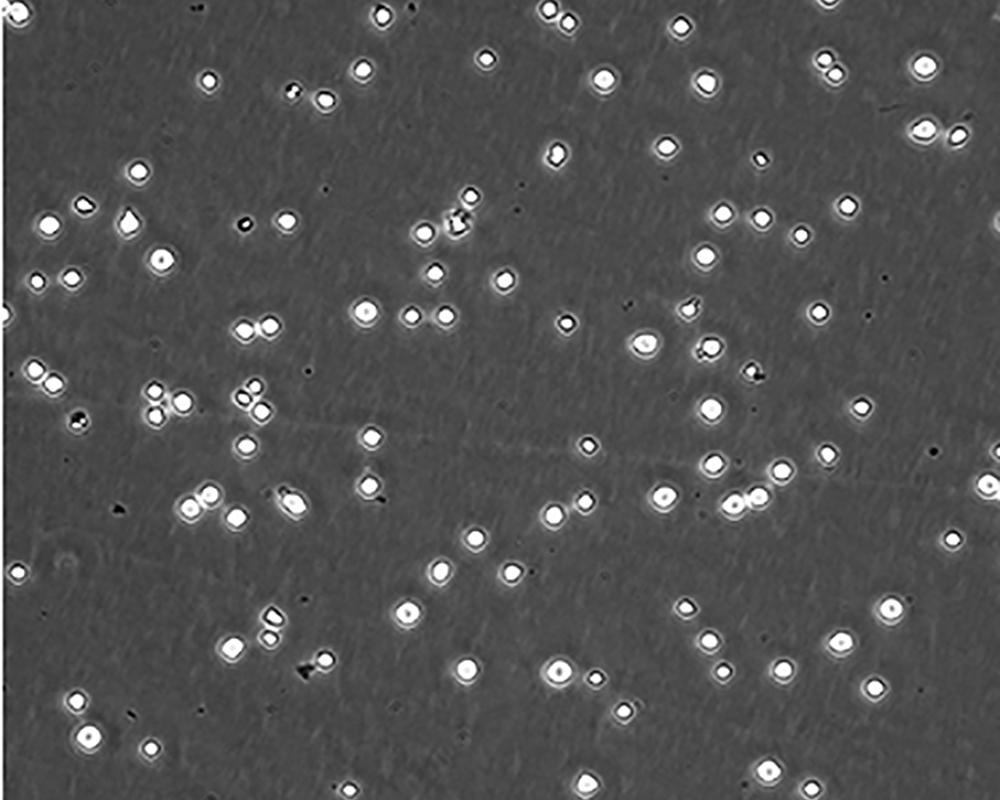

細胞描述 CEM/C1是人T細胞白血病細胞株CCRF-CEM(見ATCC CCL-119)具有喜樹堿抗性的衍生株。1991年細胞株選擇并亞克隆了對CPT的抗性。細胞表現出對CPT類似物水溶性的托泊替康和非水溶性的9-氨基-CPT及10,11-亞甲二氧基-CPT具有交叉抗性。CEM/C1細胞對CPT的敏感性較母系CEM細胞低31倍。CEM/C1細胞表現非典型的多藥抗性和轉換拓補異構酶I催化活性。對CPT的抗性維持6個月以上。